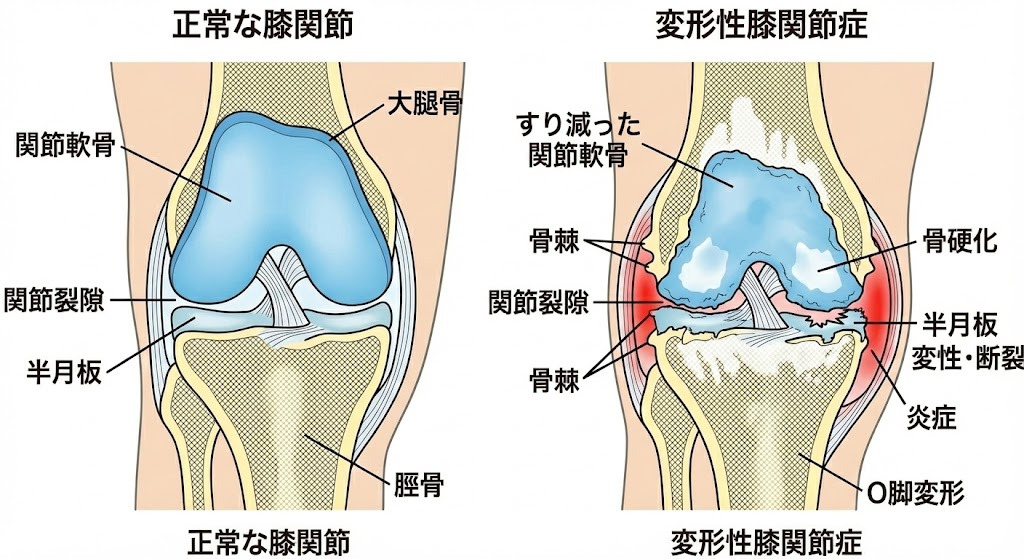

変形性膝関節症とは

変形性膝関節症は、膝関節のクッションの役割をしている「軟骨」が、加齢や長年の使用によってすり減り、膝の痛みや炎症、関節の変形(O脚など)が起こる病気です。運動器の障害によって移動機能が低下する「ロコモティブシンドローム」の主要な原因の一つでもあります。

病気が進行すると、軟骨がさらにすり減って関節の隙間が狭くなり、骨の縁に「骨棘(こつきょく)」というトゲができたり、骨が硬くなったりします。また、半月板が傷ついたり、周囲の筋肉や靭帯が弱くなったりすることで、症状がさらに悪化します。